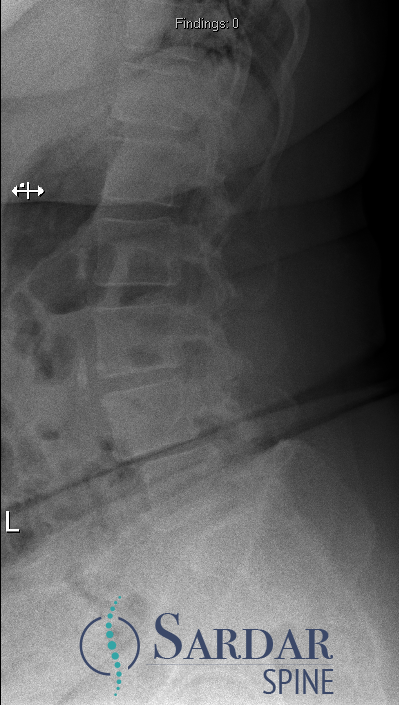

Case 1, Part 2: The patient had a #Vertiflex procedure done elsewhere; symptoms worsened, now can't stand upright, uses walker. Thoughts on her treatment so far? Next steps? #MedTwitter #Orthopedics #orthopedicsurgery #neurosurgery #spine #spinehealth #spinesurgery #scoliosis

55F with back pain and neurogenic claudication. Despite PT and epidural injections, relief is temporary. Difficulty walking long distances due to pain. What treatment would you offer next? #MedTwitter #SpineHealth #NeurogenicClaudication #spine